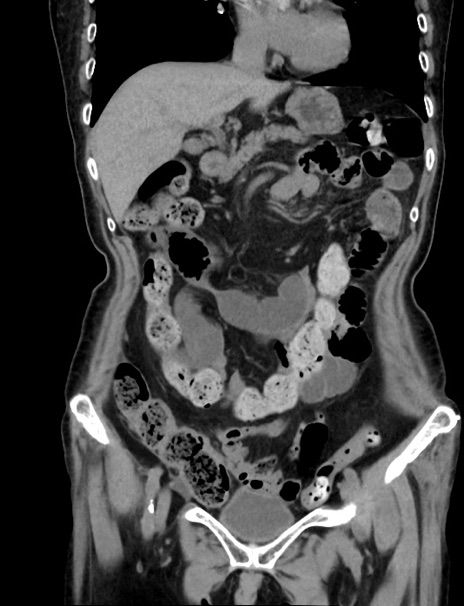

症例33(冠状断像)

【症例】70歳代 女性

【主訴】心窩部痛

【現病歴】延髄病変の精査・加療にて神経内科入院中。本日より心窩部痛あり。

【身体所見】右下腹部を中心に圧痛と反跳痛あり。

【データ】WBC 10900、CRP 0.02